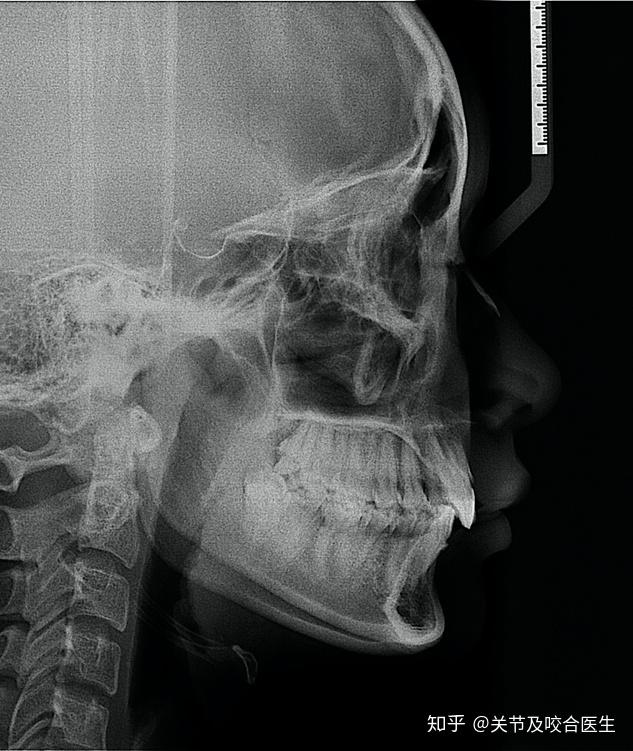

这张片子就是牙性骨性混合存在的,因为骨性程度严重,只能通过正畸 正

图片尺寸698x652